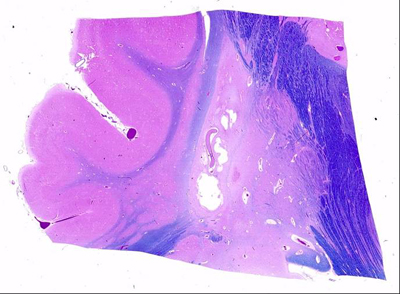

Deep grey nuclei

- bilateral lesions of basal ganglia and thalamus found in most children with cerebral palsy and severe acute HII at term

- most metabolically active areas in term infants

- especially ventro-lateral nuclei of thalamus and posterior lentiform nuclei

- associated with edema and nuclear pyknosis in the posterior limb of the internal capsule (PLIC)

- acute phase - dusky, red-brown discoloration from vascular congestion/proliferation

- chronic phase - firm, white, gliotic with tiny cystic cavities, widening of 3rd ventricle

- histology similar as above

- neurons with eosinophilia, nucleolysis and necrosis

- glial cells pyknotic and karyorrhectic

- gliosis and neuronal loss with mineralization of neurons

- Status marmoratus

- marbled appearance of deep nuclei after 6 months of age

- also seen on MRI

- result of term damage with gliosis and aberrant myelination of glial fibers